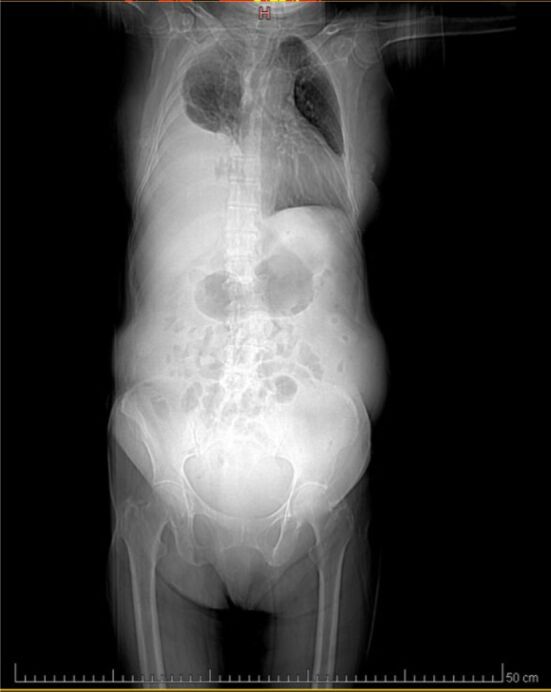

Abstract Image